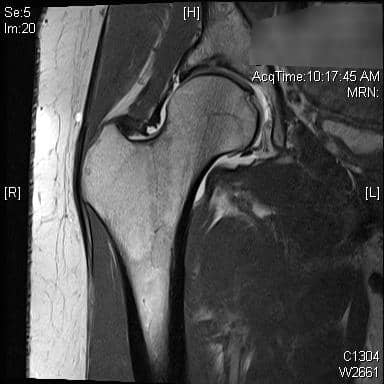

एमआरआई और सीटी का उपयोग एसिटाबुलम और समीपस्थ फीमर के आगे के मूल्यांकन के लिए किया जा सकता है। ये अध्ययन एसिटेबुलर संस्करण और नरम ऊतक के प्रभाव का बेहतर मूल्यांकन प्रदान कर सकते हैं या प्रीऑपरेटिव प्लानिंग में मदद कर सकते हैं। एमआर आर्थ्रोग्राम ऊरु गर्दन के कैम घाव के निदान में भी सहायता कर सकता है, लैब्रम या उपास्थि का आकलन कर सकता है। रेडियल अनुक्रमण सबसे अच्छा है, एक असामान्य लैब्रम कुंद दिखाई देगा या इसके आधार पर बढ़े हुए संकेत के साथ दिखाई देगा। 3, 4 एसिटैबुलर रेट्रोवर्जन के कारण पिंसर का प्रभाव, शुरू में लैब्रल विफलता दिखाएगा, जिसके बाद एक कॉन्ट्राकूप तंत्र के परिणामस्वरूप पोस्टरोहीन एसिटेबुलर कार्टिलेज में छोटे, पतले घाव होंगे। 5 इसे क्रॉस-ओवर संकेत, पीछे की दीवार के संकेत, या रेडियोग्राफ़ पर एक नकारात्मक खट्टा कोण के साथ पुन: प्रदर्शित किया जा सकता है। एमआरआई में कुंद लैब्रम, ऊरु गर्दन पर चुंबन घाव, पीछे के एसिटेबुलर कार्टिलेज का घिसना, या एक रेट्रोवर्टेड एसिटाबुलम प्रदर्शित होगा। ऊरु गर्दन के घावों के कारण कैम का प्रभाव, उपास्थि की प्रारंभिक विफलता को दर्शाता है, जिसके बाद लैब्रल फट जाता है। पार्श्व एक्स-रे पर सिर-गर्दन ऑफसेट में कमी, ऊरु गर्दन पर अतिरिक्त हड्डी की आकृति और बढ़े हुए अल्फा-कोण का आकलन निदान में सहायता कर सकता है। एमआरआई पर लैब्रम अपने आधार पर फटने का प्रदर्शन कर सकता है, एक असामान्य ऊरु सिर-गर्दन समोच्च स्पष्ट हो सकता है, या उपास्थि प्रदूषण स्पष्ट हो सकता है। रोगी 80% मामलों में कैम और पिंसर दोनों के साथ पेश होंगे, हालांकि एक रूप आमतौर पर प्रमुख होता है। 2

रोगी एक 39 वर्षीय महिला है जिसमें महत्वपूर्ण दाहिने कूल्हे का दर्द है जो गैर-प्रभाव लोडिंग व्यायाम, गतिविधि संशोधन और स्टेरॉयड इंजेक्शन के साथ रूढ़िवादी उपचार के बावजूद बना रहता है। वह गहरी कुर्सियों से बाहर निकलने और धुरी गतिविधियों से सबसे ज्यादा परेशान है। उनका एमआरआई किया गया था, जिसमें लैब्रल टियर दिख रहा था।